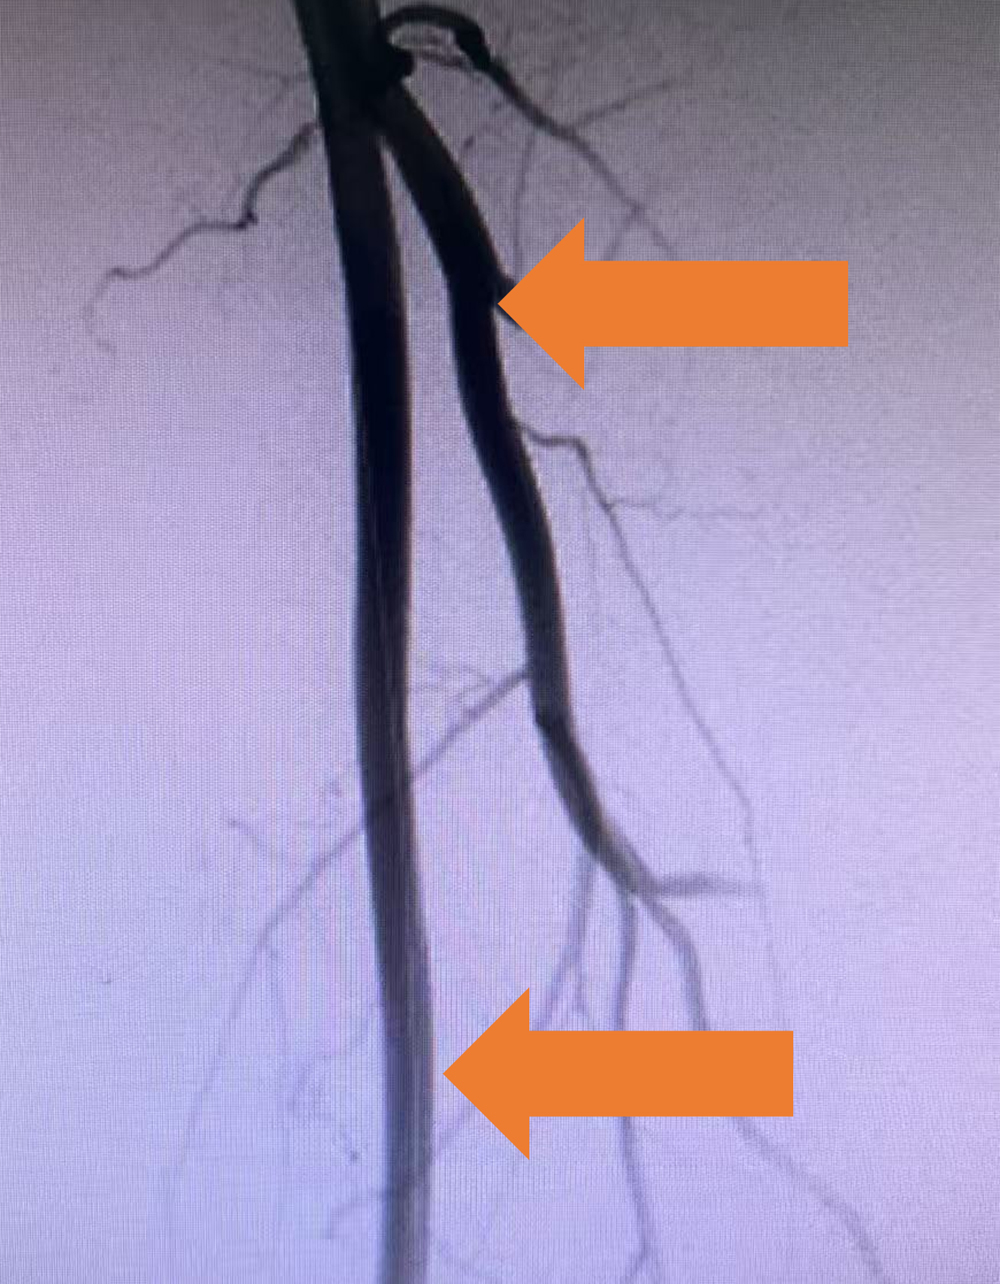

取栓后 左下肢动脉造影,显示股浅动脉及股深动脉血流均恢复